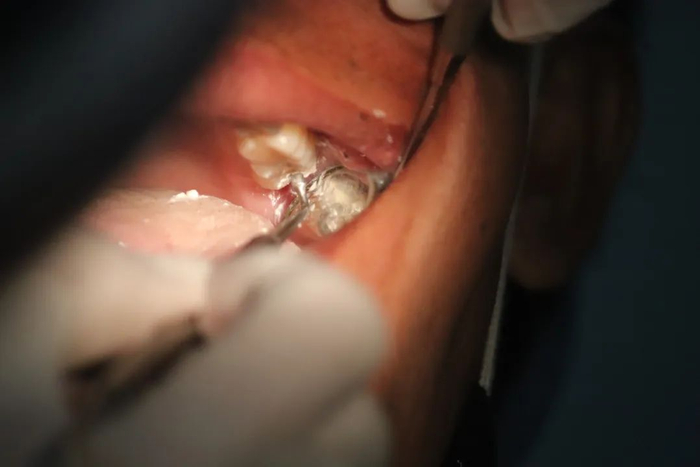

口腔黑色素瘤长啥样?

相比于脸上、脖子、手臂等发生在皮肤上的黑色素瘤,长在口腔的黏膜黑色素瘤很少被大家注意到,大部分在前期也没有什么不适的症状

等到发现时,它已“默默地”向深部组织浸润,侵犯深层黏膜以及骨组织,引起牙齿松动,口腔内肿块还会出现溃烂、出血、剧烈疼痛,并且容易发生颈部淋巴结以及全身肿瘤转移,甚至最终危害生命。

从颜色上看:口腔黑色素瘤表现为明显的蓝黑色结节状肿块。

从生长速度看:口腔黑色素瘤生长速度十分迅猛,颜色加深,并向四周扩散生长。

从形态上看:一般表现为斑点或者结节状,表面常溃烂。

从发病位置看:口腔恶性黑色素瘤大多数出现在上牙龈以及硬腭,也有部分病例病变位置出现在颊部、舌部以及唇部。